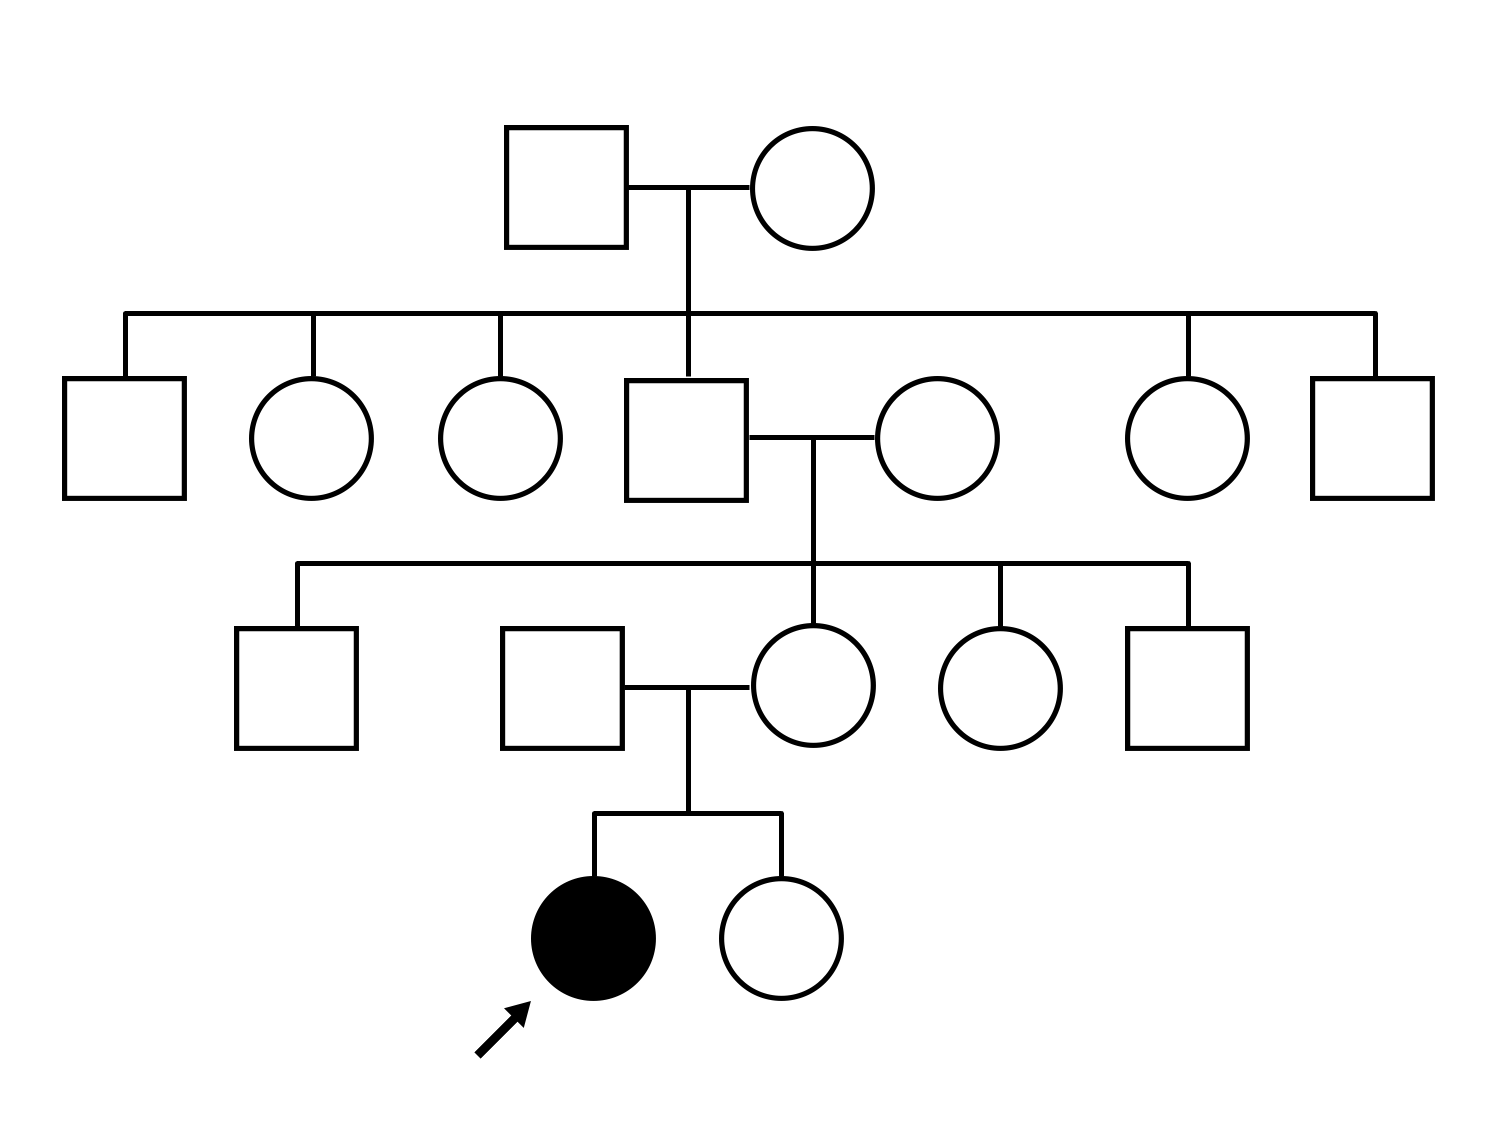

AR Stargardt Disease (IIA)

AR Stargardt Disease (IIA)

This 11 year old female first had difficulty seeing the blackboard at age 8. Later, she developed some photophobia.

Diagnosis & molecular findings

| Disease | Gene | Allele 1 variant(s) | Allele 2 variant(s) | Inheritance mode |

|---|---|---|---|---|

| AR Stargardt Disease | ABCA4 | Gly1961Glu GGA>GAA, Arg212Cys CGC>TGC | Gly1961Glu GGA>GAA, Arg212Cys CGC>TGC | AR |